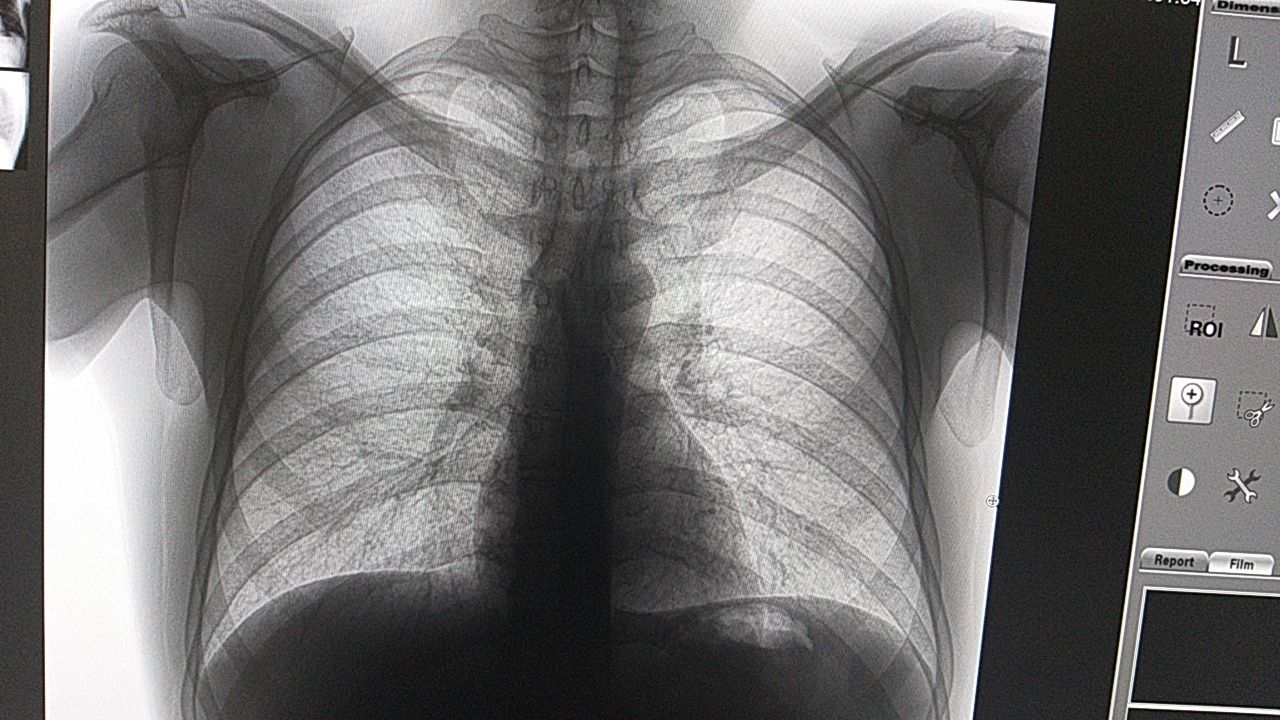

Nikita Levin

Анамнез клиника

Кашель 3 месяца.

Возраст

Температура?

Нет